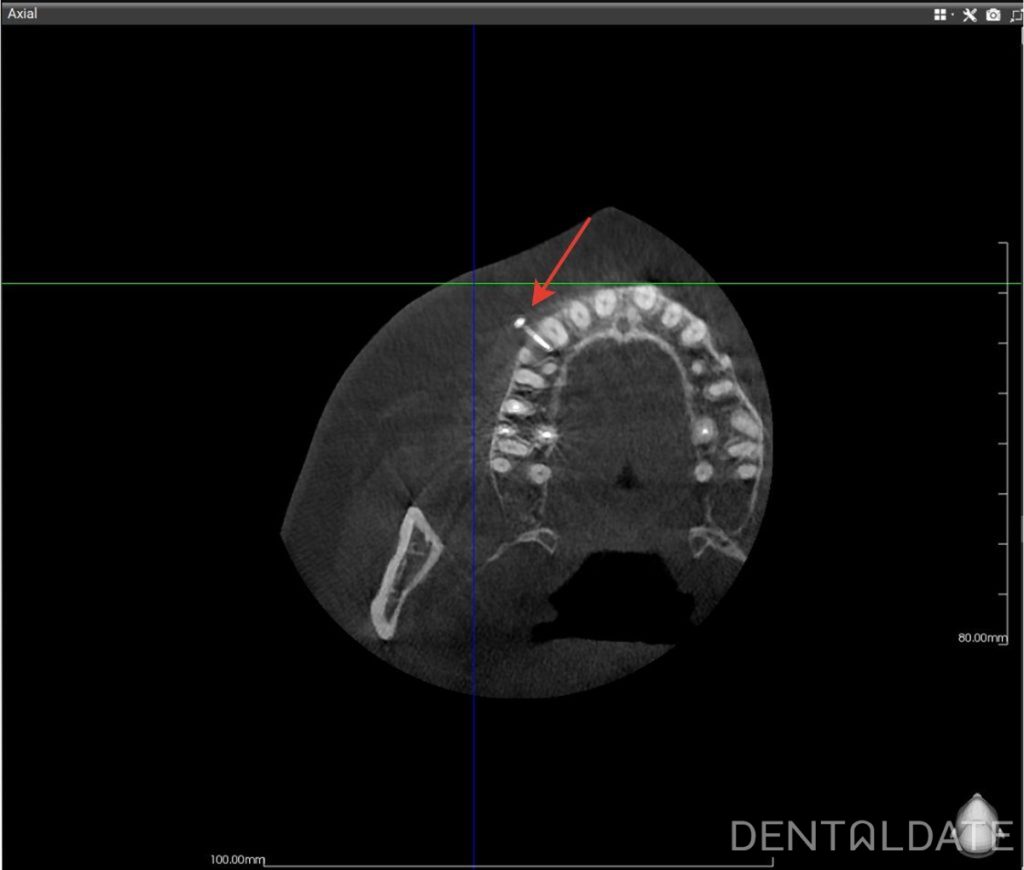

This case demonstrates the placement of an interradicular miniscrew. The procedure is performed under local anesthesia and is completely painless. The procedure, from the administration of anesthesia to the control radiograph, takes approximately 10 minutes. Screw position is verified using cone-beam computed tomography (CBCT), currently considered the gold standard in dentistry.